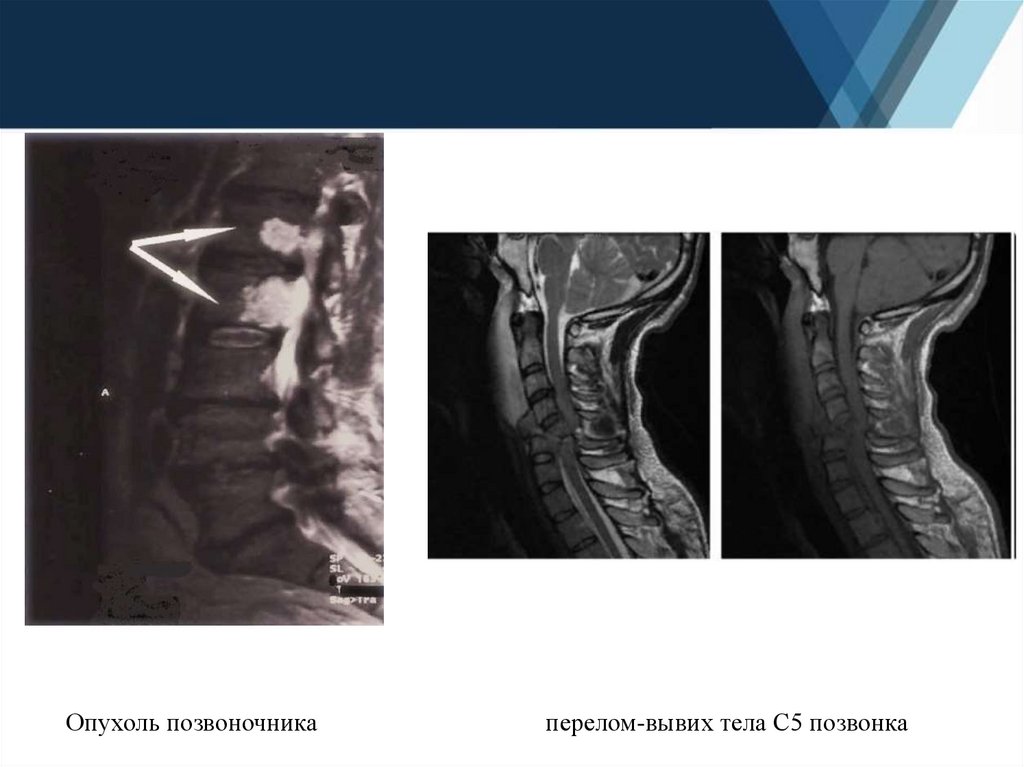

12.

Опухоль позвоночника

перелом-вывих тела С5 позвонка